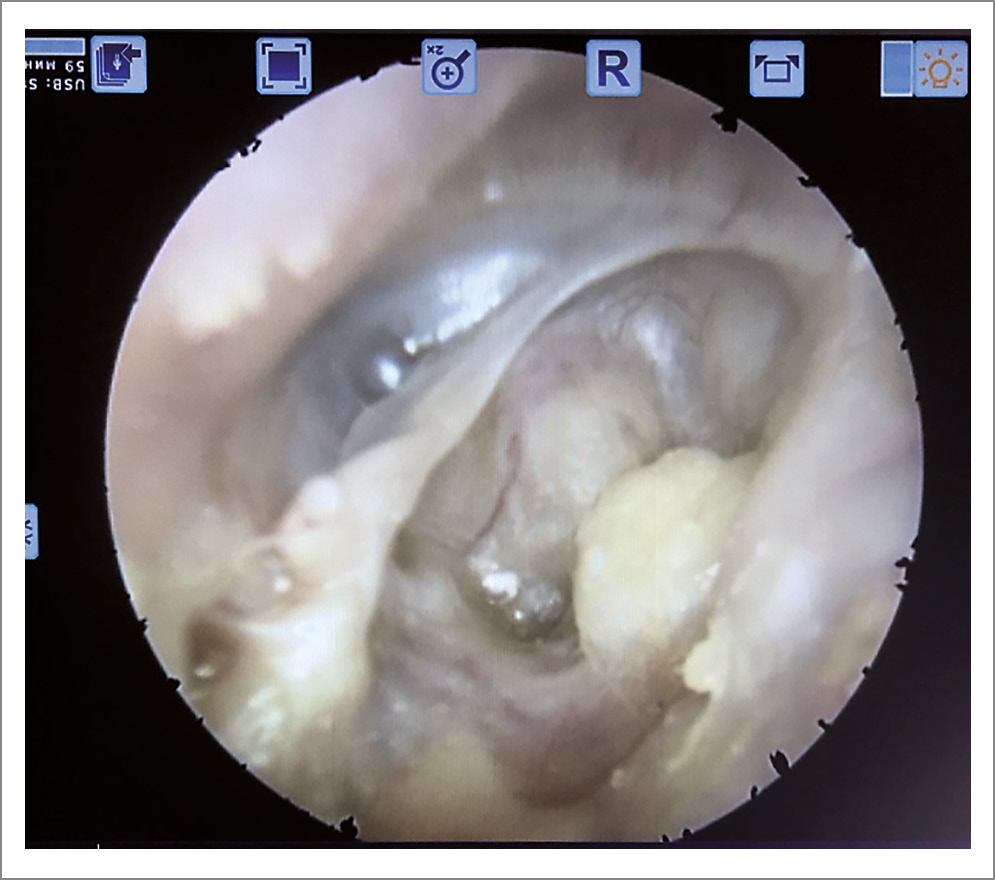

Функционально, т.е. с позиции восстановления слуха, ситуация становится еще более негативной. Так как трансплантат барабанной перепонки помещается на канал лицевого нерва и медиальную стенку аттика, то отмечается два нюанса: существенное уменьшение объема тимпанальной полости и формирование большого пространства латеральнее барабанной перепонки, включающего мастоидальную полость и сосцевидный отросток. Исходя из того, что объем тимпанальной полости является частью физиологии слуховой трубы, то по закону Бойля–Мариотта определенное перемещение объема из большого объема сопровождается меньшим изменением давления, чем при изъятии такого же объема из малого исходного объема. Иными словами, постоянная абсорбция газов из малой тимпанальной полости будет оказывать более сильное влияние на давление в среднем ухе. Таким образом, трансплантат барабанной перепонки будет подвержен большему влиянию к пролабированию медиально, и, следовательно, вероятность фиксации трансплантата к промонториальной стенке будет значительно больше. К. Flisberg в своих работах отмечал, что при тимпанальной полости малого объема отделение подвижных стенок слуховой трубы друг от друга затрудняется ввиду относительно более выраженного снижения давления в среднем ухе к моменту открытия слуховой трубы. При дальнейшем нарастании отрицательного давления свыше 30 мм рт. ст. в тимпанальной полости малого размера возникает патологический круг, при котором открытие слуховой трубы становится невозможным за исключением продувания трубы повышенным давлением через носоглотку. Барабанная перепонка втягивается и фиксируется к медиальной стенке тимпанальной полости, что влияет на итоговую потерю передачи звука (рис. 4).

Рис. 4. Трансканальная эндоскопическая картина результата выполненной радикальной операции с тимпанопластикой. Неотимпанальная мембрана спаяна с медиальной стенкой барабанной полости.